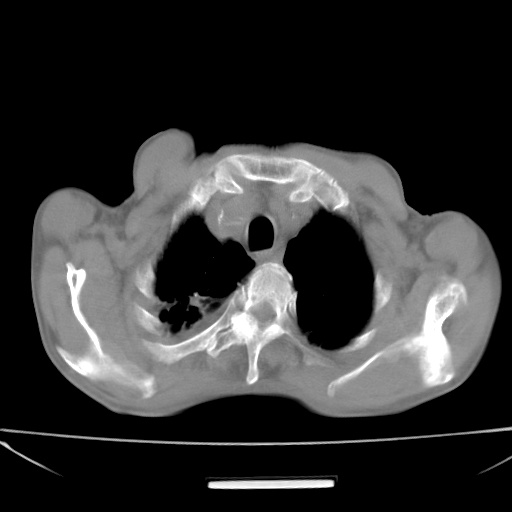

标题: CT13796:请会诊右上费病变!

患者男80岁,反复咳嗽多年,咳喘伴咯血1月

右上肺周围型肺癌伴肺门淋巴结转移.右上肺继发型肺结核.

右上肺周围型肺癌伴肺门淋巴结转移

右肺上叶占位性病变,考虑周围型肺癌,肺门淋巴结转移。要是能提供更多的临床资料就好了,以供鉴别诊断。

右肺尖周围型肺癌伴肺门淋巴结肿大

右肺尖结核

右肺上叶占位性病变,考虑周围型肺癌,肺门淋巴结转移。

右上肺周围型肺癌伴肺门、纵膈淋巴结转移

考虑为:右肺上叶肺癌伴阻塞性肺炎、右肺门及纵膈淋巴结转移。